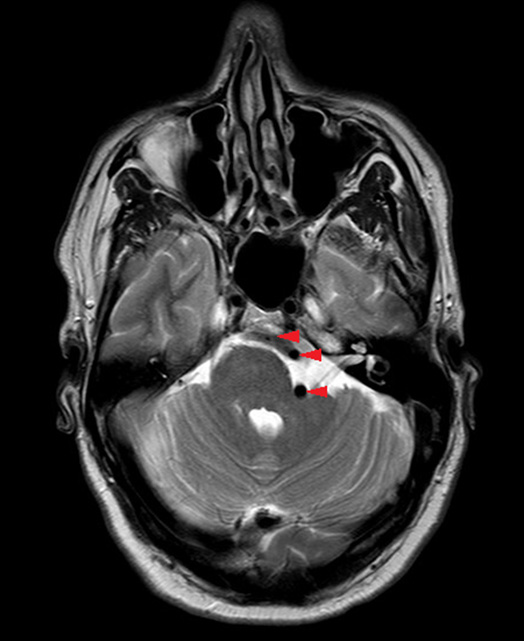

A 50-year-old gentleman presented with a six month history of left sided, high pitched, continuous, nonpulsatile tinnitus with mild left sided hearing loss. He did not complain of any other otogenic symptoms and his past medical history was unremarkable. Otoscopy and cranial nerve examination were normal. His audiogram showed left high frequency sensorineural hearing loss with an average hearing threshold of 40 dB (Figure 1). An MRI IAM was organized that revealed VBD causing significant distortion and deviation of the left VI, VII, and VIII nerve complex at the level of the pontomedullary junction as well as localized mass effect and displacement of the brain stem (Figure 2). The case was discussed at the skull base multidisciplinary team meeting. Surgical intervention was not advised as the vertebral artery was not in direct contact with VIIIth nerve. As the patient’s quality of life was unaffected by his symptoms, the risks of surgery were outweighed by the benefits. No intervention was made and the patient was discharged as per their request. The patient’s general practitioner (GP) was advised to review and manage modifiable risk factors for ischemic stroke and refer to the stroke team for consideration of antiplatelet therapy.

Figure 2: Magnetic resonance image showing dolichoectatic left vertebral artery at the level of the pontomedullary junction. This elongated, tortuous, and dilated artery is causing significant brain stem deviation as demonstrated by the image. Red arrow heads track the course of the left vertebral artery.